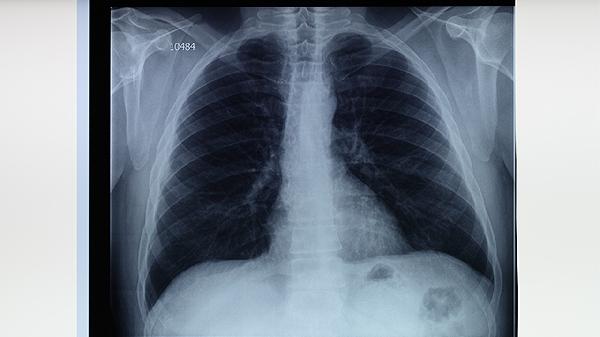

糖尿病患者、矽肺患者、免疫抑制劑使用者等應(yīng)每年進(jìn)行胸部X線檢查。結(jié)核病密切接觸者需在暴露后第0、3、6個月進(jìn)行癥狀監(jiān)測和影像學(xué)復(fù)查。結(jié)核菌素試驗強陽性者可在醫(yī)生指導(dǎo)下開展預(yù)防性化學(xué)治療。